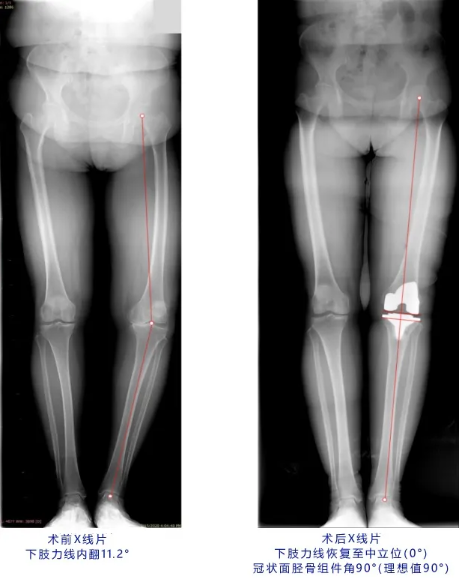

本次手术患者为一名63岁女性,罹患膝关节重度骨关节炎十余年,关节周围有大量骨赘增生,关节内翻畸形。为使患者获得最佳的手术效果,该手术团队术前进行了多次讨论,最终采纳并使用了人工智能个性化术前规划。

术中,术者参考三维术前规划中标明的下肢力线、股骨外翻角、股骨外旋角、截骨厚度等关键参考指标,精准实现术前计划。在该手术方案的帮助下,手术操作全程耗时仅45分钟,所用假体型号、角度与术前计划完全一致,膝关节内外侧间隙、屈伸间隙平衡,髌骨轨迹及关节活动度良好,术后复查X线片,示假体位置良好,下肢力线恢复至中立位。